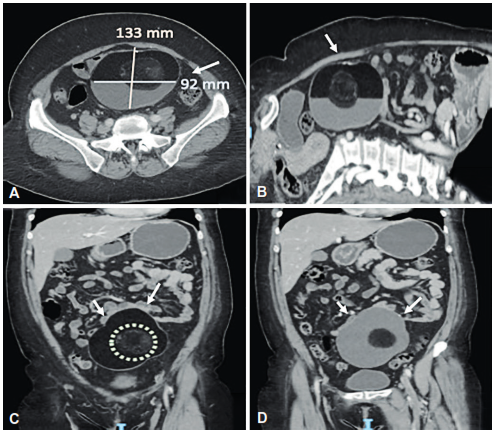

Paciente femenina de 56 años, con antecedente de carcinoma ductal infiltrante de mama izquierdo estadio clínico IIA (T2N0M0), en remisión. En los estudios de seguimiento por cirugía de mama y tejidos blandos, observaron como hallazgo incidental en la tomografía computarizada (TC) de abdomen, una lesión voluminosa, de aproximadamente 133x127x92 mm, de localización abdominopélvica, contornos definidos, de contenido líquido y graso, con presencia de calcificaciones en su periferia (Figura 1).

Figura 1. Tomografía de abdomen contrastada. Corte axial (A) y corte sagital (B), donde se observa una lesión bien definida, dependiente del mesenterio, a nivel del mesogastrio, con contornos lisos y nivel grasa-líquido. Corte coronal (C) que muestra la lesión dependiente del mesenterio y un nódulo en su interior (D), con densidad heterogénea, de aproximadamente 49x51x64 mm.